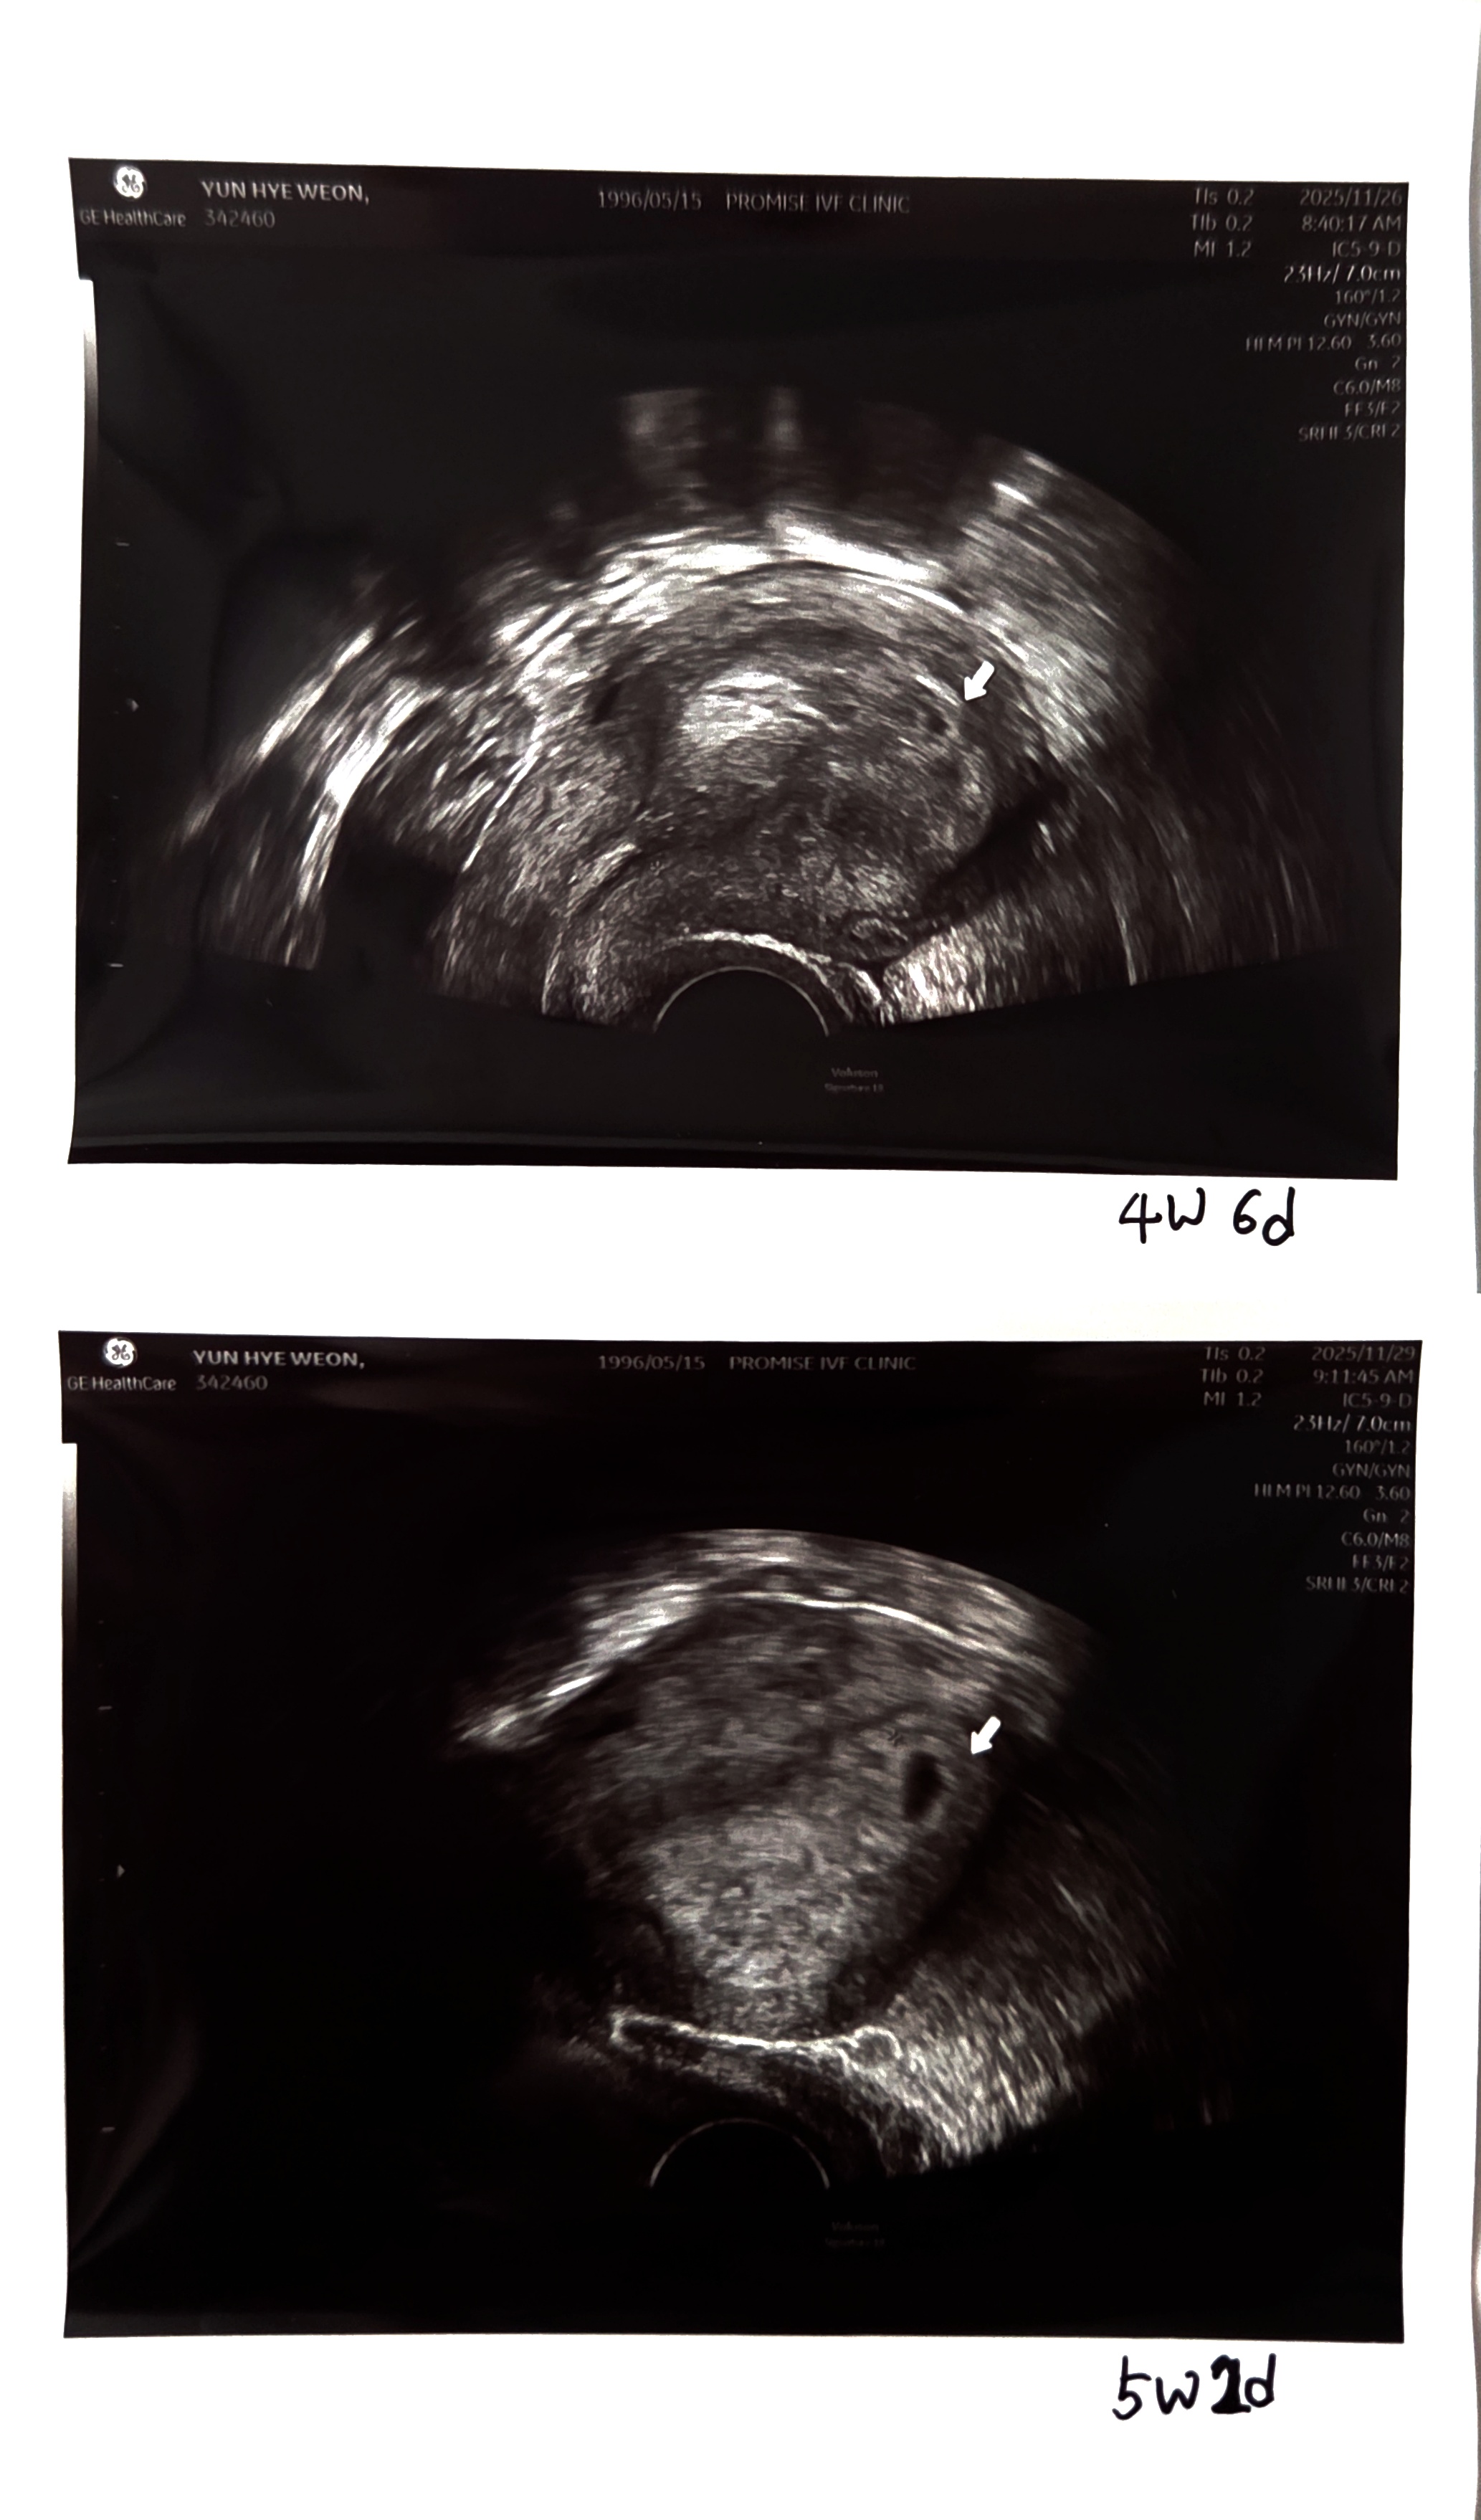

저는 96년생인데 다낭성이 심해서 난임병원을 다녔고, 호르몬 불균형이 심해서 맞추고 임신하는데까지 3개월은 걸릴거다 하셨는데 실제론 병원다니고 첫 시도만에 임신이 되었어요. 배란주사를 맞고 날짜도 정확히 그때만 관계를 했기때문에 배란일도 정확히 알고있어서 배란일이 늦었다거나 그런일은 없어요! 11월 5일날 배란주사를 맞고 11월 6일~7일 사이에 배란이 되었을것으로 예상하고 있습니다. 4주 6일차와 5주 2일차에 초음파 검사를 했을때, 아기집이 3배이상 커져서 건강하게 잘 크고있다고하셨는데 어지러운 것도, 생리통처럼 배아픈것도, 소화가안되던것도, 변비도 다 5주 말부터 사라졌어요. 6주 2일차에 다이아몬드링 볼수있을것같다고 초음파보러오라고 하셨는데 너무 불안하네요ㅜㅜ 사람마다 증상이 다르긴하지만 유산한 사람들의 브이로그를 보면 입덧이 대부분 없던데ㅜㅜ 저처럼 아무 증상없으셨던 분 계신가요? 호르몬불균형때문에 유산이 된건지 잘크고있는건지 넘 불안해요ㅜㅜ